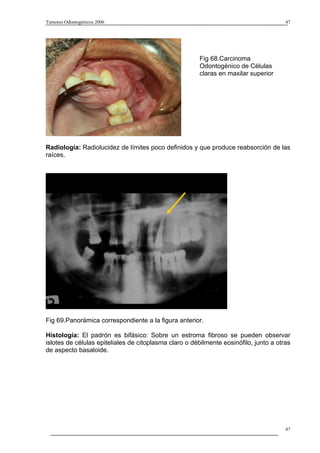

Fig 68.Carcinoma

Odontogénico de Células

claras en maxilar superior

Radiología: Radiolucidez de límites poco definidos y que produce reabsorción de las

raíces.

Fig 69.Panorámica correspondiente a la figura anterior.

Histología: El padrón es bifásico: Sobre un estroma fibroso se pueden observar

islotes de células epiteliales de citoplasma claro o débilmente eosinófilo, junto a otras

de aspecto basaloide.